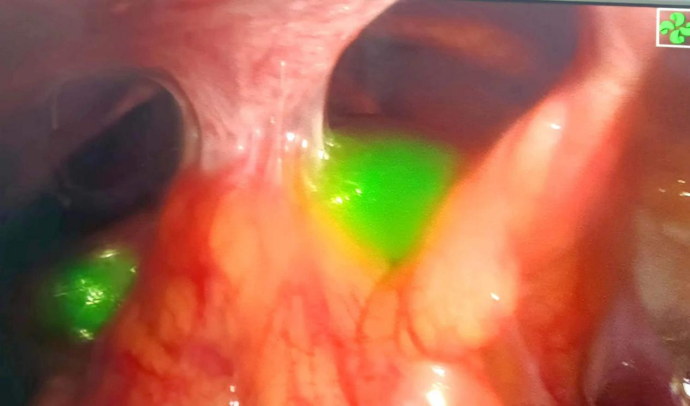

肝脏肿瘤吲哚箐绿荧光染色术中图片

荧光腹腔镜技术是在荧光导航的指引下,几十秒内可实现组织和器官显影,精确定位肿瘤边界和发现微小病灶,做到肿瘤精准切除,淋巴节清扫更彻底。

手术由杨志坚、黄芳医师双主刀模式执行,麻醉科、手术室密切配合,历时3个多小时,完整切除胆囊及肝脏4b+5段并清扫周围淋巴结。术中荧光引导标记肿瘤切缘,在麻醉科谢广晨医师实施低中心静脉压技术的帮助下,出血不足100ml。在围手术期通过快速康复外科流程,患者术后基本无腹水。病理证实为胆囊低分化腺癌,淋巴结未见转移。术后6天患者顺利出院。